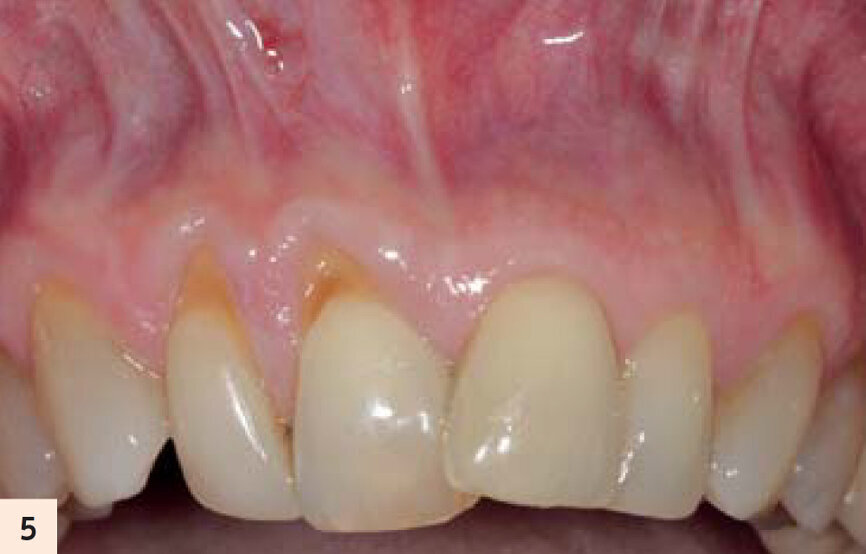

figure 5 : Vue préop. Récession traumatique de classe II Miller avec malposition dentaire associée.

L’incision muqueuse verticale permet l’instrumentation horizontale (mesio-distale) et apico-coronaire d’un lambeau de pleine épaisseur, ce qui entraine le relâchement total et le déplacement coronaire passif du complexe muco-gingival papillaire (Figs. 5, 6).